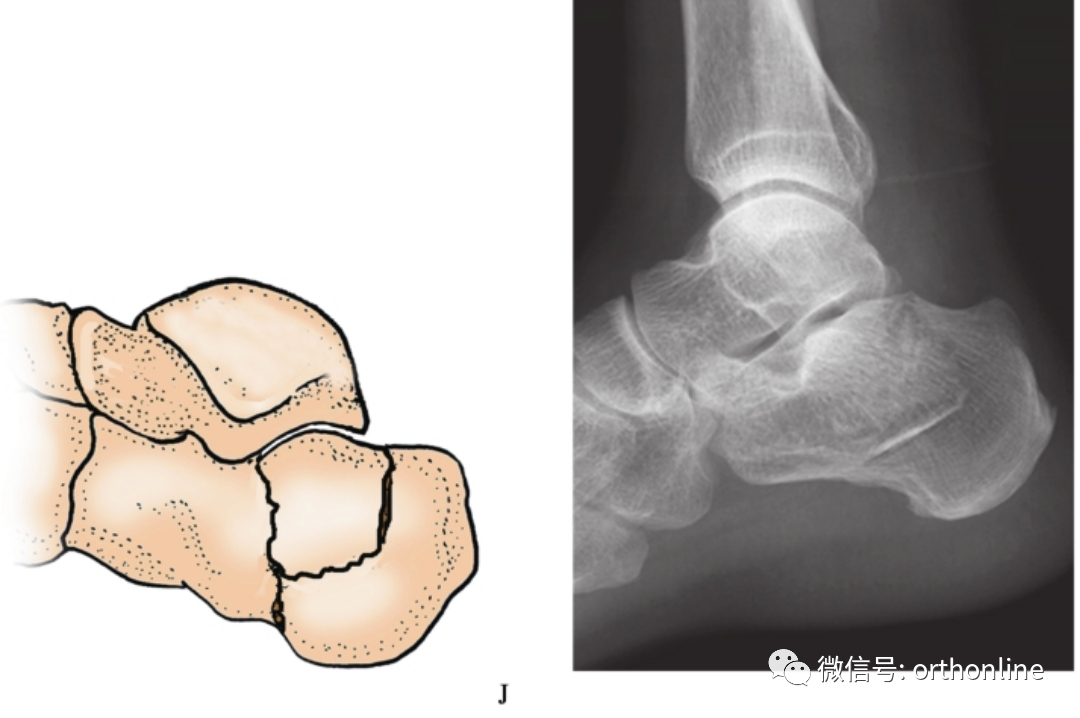

多图详解5种常见跟骨骨折分型